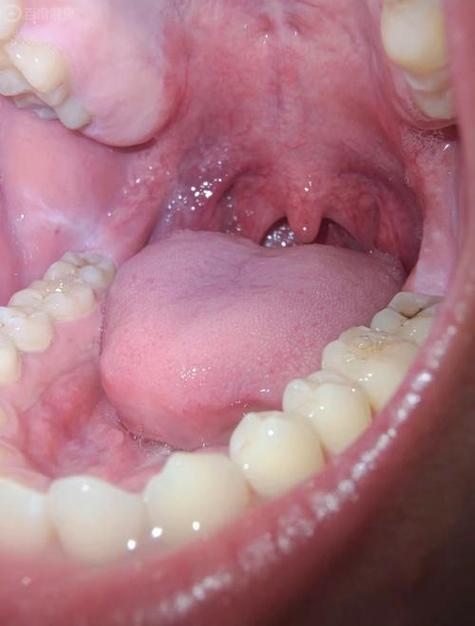

(图片来源网络,侵删)

这是最核心的症状,主要发生在口腔黏膜的任何部位,最常见于颊黏膜(内腮帮子),其次是舌部、牙龈、唇部、硬腭等。

- 网纹型: 这是最典型的表现,黏膜上出现微小的白色或灰白色条纹,这些条纹交织成网状、树枝状或线状,像蕾丝花边一样,周围的黏膜可能正常或轻微发红。

- 丘疹型: 黏膜上出现针头大小、半透明的丘疹,散在或成簇分布,当这些丘疹融合成片时,就形成了网纹型。

- 斑块型: 出现界限清晰的、白色或灰白色的、稍高于黏膜表面的斑块,质地较硬,类似白斑,需要警惕癌变风险。

- 糜烂/溃疡型: 这是最严重、症状最明显的一种,在网纹或斑块的基底上,出现破溃、糜烂,形成浅表性的溃疡,患者会感到明显的疼痛,尤其在进食辛辣、酸性食物时加剧。

- 萎缩型: 黏膜变薄,呈鲜红色或暗红色,有时可以看到下面红色的血管,有时伴有白色条纹。

- 水疱型: 比较少见,黏膜下出现透明的小水疱,水疱破溃后也会形成糜烂面。

颜色

病变区域通常呈现白色、灰白色或珍珠色,这是由于黏膜下固有层中的炎症细胞浸润,使上皮角化过度所致。